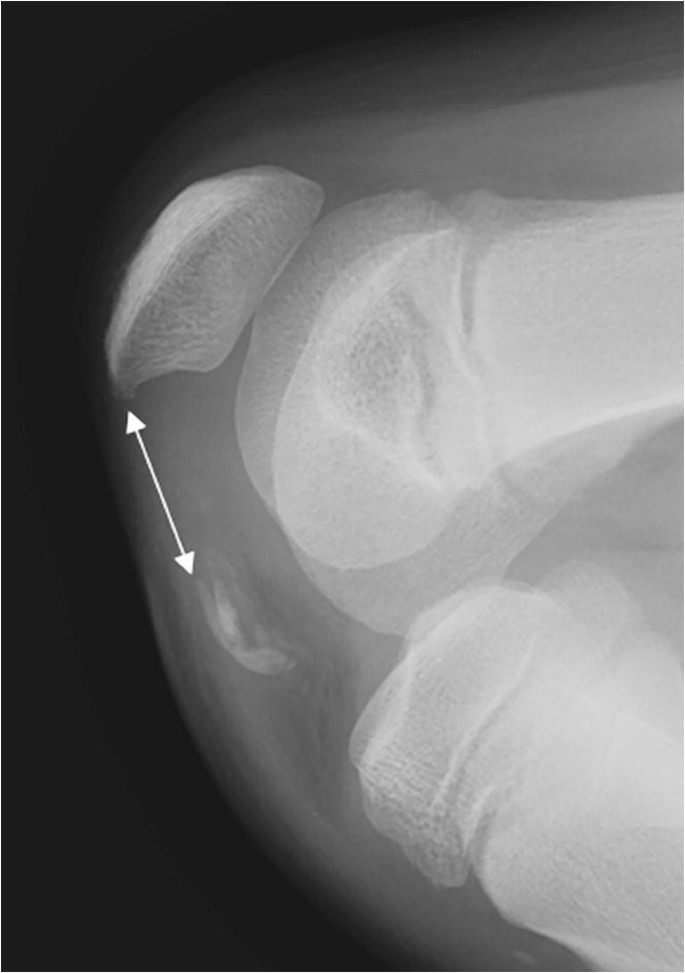

Bowing Fracture Definition